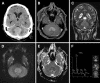

Primary central nervous system lymphomas (PCNSL) are rare CNS tumors that harbor a conspicuously longer diagnostic delay compared to other malignant brain tumors. The gold standard for diagnosis is stereotactic biopsy to acquire tissue for histopathological analysis and therefore neurosurgery plays a central role when reducing the diagnostic period is mandated. However, histopathological diagnosis could be complicated if the patient was preoperatively exposed to corticosteroids. Besides the histopathological result, diagnosis of a PCNSL also requires full diagnostic workup to exclude cerebral metastatic disease of a systemic lymphoma. Most reviews of PCNSL discuss recent advancements in systemic treatment options from an (neuro-)oncologic viewpoint, whereas our intention was to discuss the optimization of the diagnostic period and therefore describe current standards of imaging, summarizing the diagnostic workup, discussing the surgical workup and future diagnostic prospects as well as the influence of preoperative corticosteroid therapy to reduce the diagnostic delay of PCNSL patients.